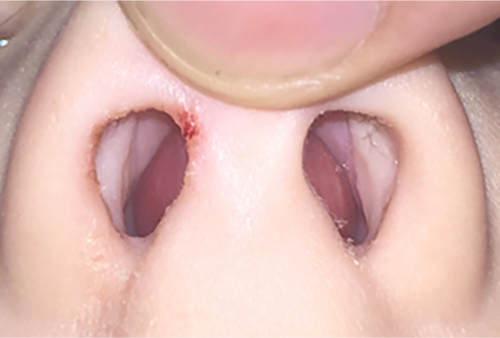

• Nasal septal haematoma

• Suggested by deviation/asymmetry, swelling, or discolouration of the septum

• Assess via direct visualisation of septum by anterior rhinoscopy with otoscope/headlamp/loupes and nasal speculum

• Suction away clots

• Consider use of Co-Phenylcaine spray (vasoconstriction)

• Assess by gentle palpation of nasal septum between two fingers or with a cotton applicator, feeling for fluctuance/bogginess

• Must be screened for on initial assessment, delays to diagnosis can lead to erosion/necrosis of cartilage and significant deformity

• Identification of septal haematoma mandates emergent ENT referral

Nasal haematoma_smaller

Septal haematoma